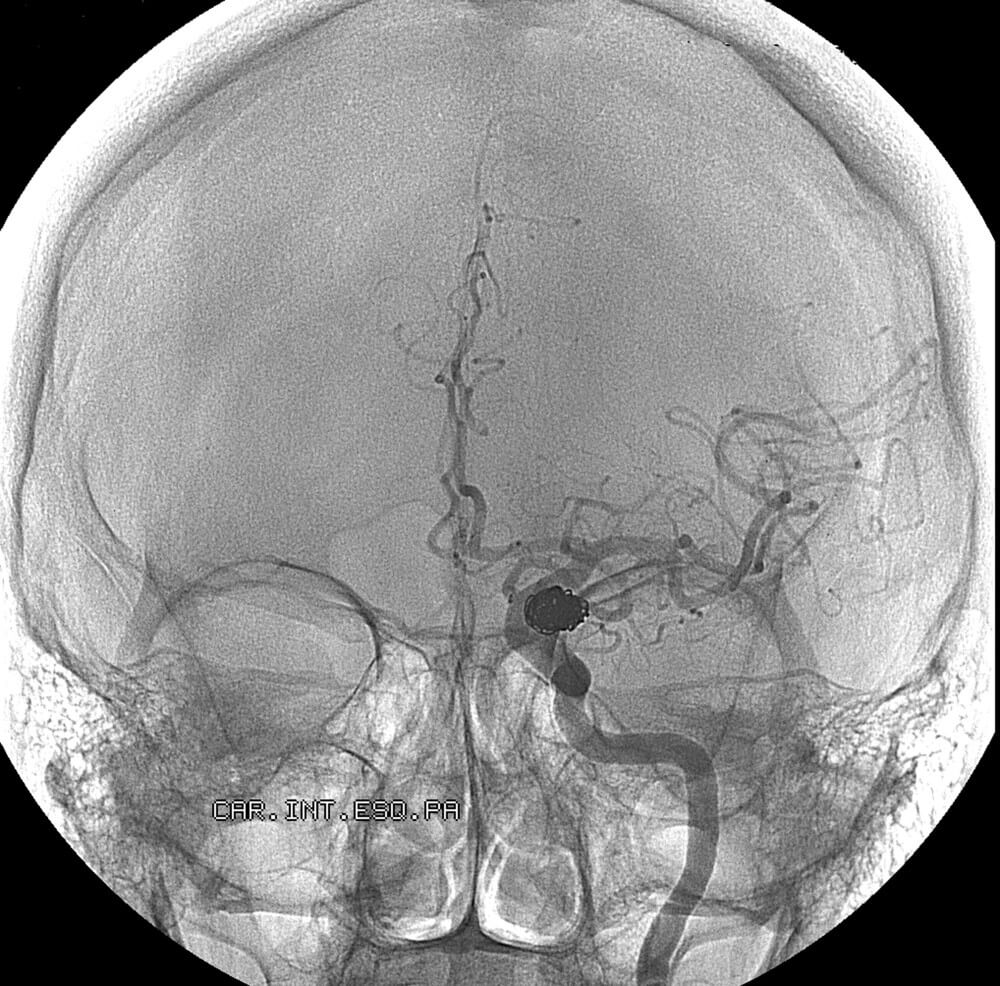

Arteriovenous malformation

There are four main types of vascular malformations: Arteriovenous malformation (AVM), Dural arteriovenous fistula (dAVF), Venolymphatic malformation, and Cerebral cavernous malformation (CCM). Vascular malformations vary significantly on their potential for damage, depending on their type and location. Some may simply be a cosmetic issue; others can be a nuisance, causing a pulsating noise called pulsatile tinnitus, while others pose a risk for brain hemorrhage, strokes, loss of vision, and death.

Embolization